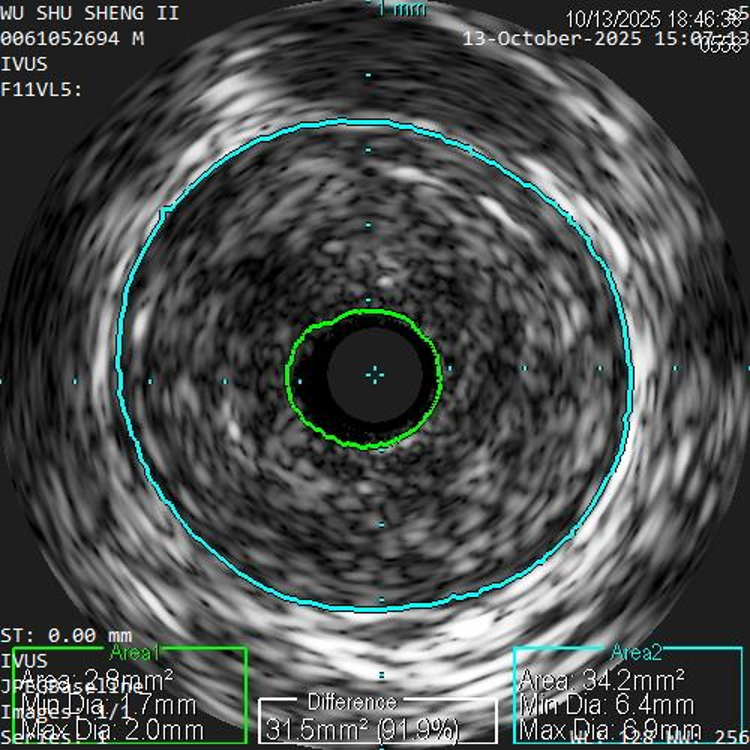

经导丝送入IVUS导管,股浅动脉近段重度狭窄、钙化明显,狭窄率大于90%

股浅动脉中远段及腘动脉重度狭窄、环周钙化明显

IVUS提示病变段仍有局部重度狭窄,遂选择最新上市的”始祖鸟”紫杉醇药物涂层球囊(5*150mm、6*150mm )对残余狭窄进行扩张